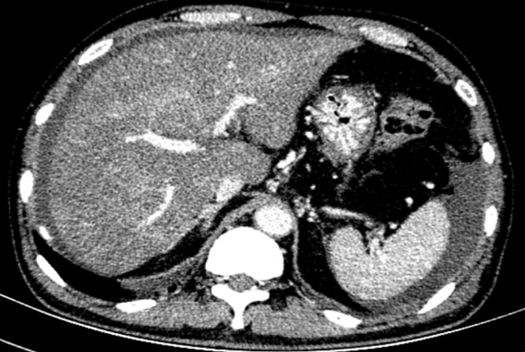

进一步检查及确诊:增强CT检查:下腔静脉肝段狭窄,内可见造影剂填充,肝脏异常强化(肝脏弥漫密度减低,门脉静脉期及平衡期显示肝脏不均匀强化,肝静脉周围呈片状明显强化,余肝实质呈轻度强化);腹部MRI:肝实质信号不均、肝静脉显示不清、腹水;肝脏病理活检:肝小叶结构未见异常,小叶中央为主的肝细胞片状退变坏死,灶性区域可见肝窦内淤血现象,形态提示缺血或淤血改变,致病因素包括药物/毒物、流出道梗阻(VOD、布加综合征)。免疫组化结果:CD34染色未见异常,CK7染色显示局部胆小管增生,局部肝细胞胆管化,HBsAg(-),特殊染色结果:Masson染色显示汇管区纤维组织增生,PAS、PAS+消化、铁、铜染色未见异常,网织纤维局部破坏。追问病史,患者起病前2月曾服用“三七粉”1月。最终诊断为吡咯生物碱相关性肝窦阻塞综合征。

MRI: